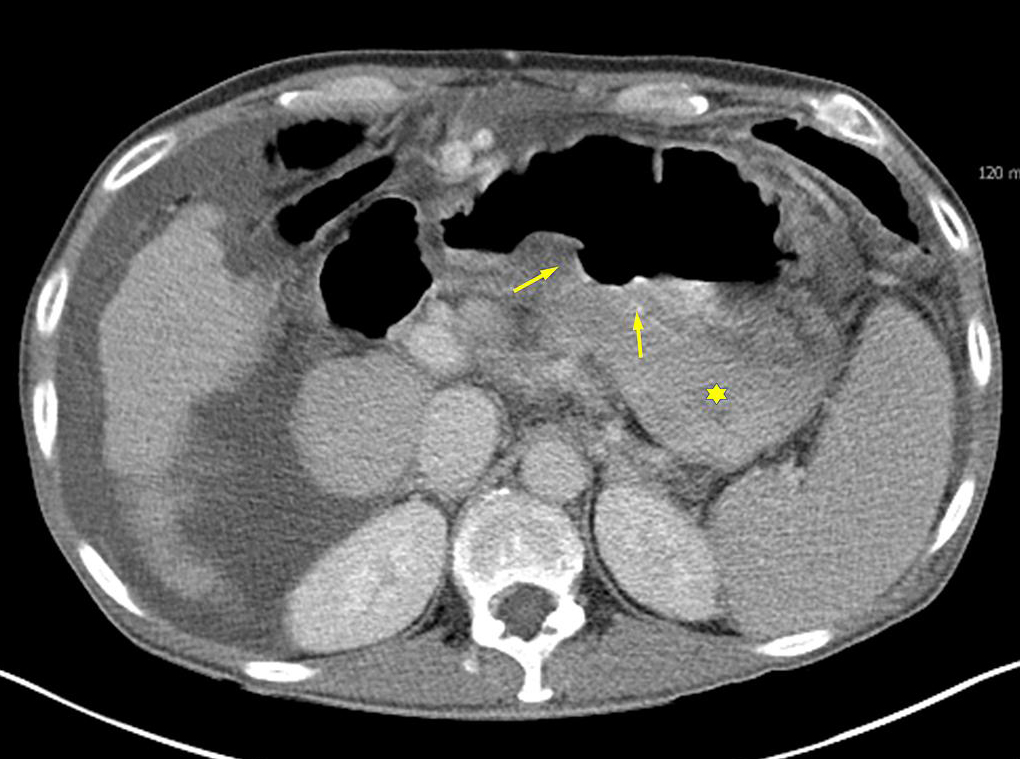

Images

de TDM scanner en coronal de ulcere gastrique a la paroi posterieure

de l'estomac ( fleche jaune ) |